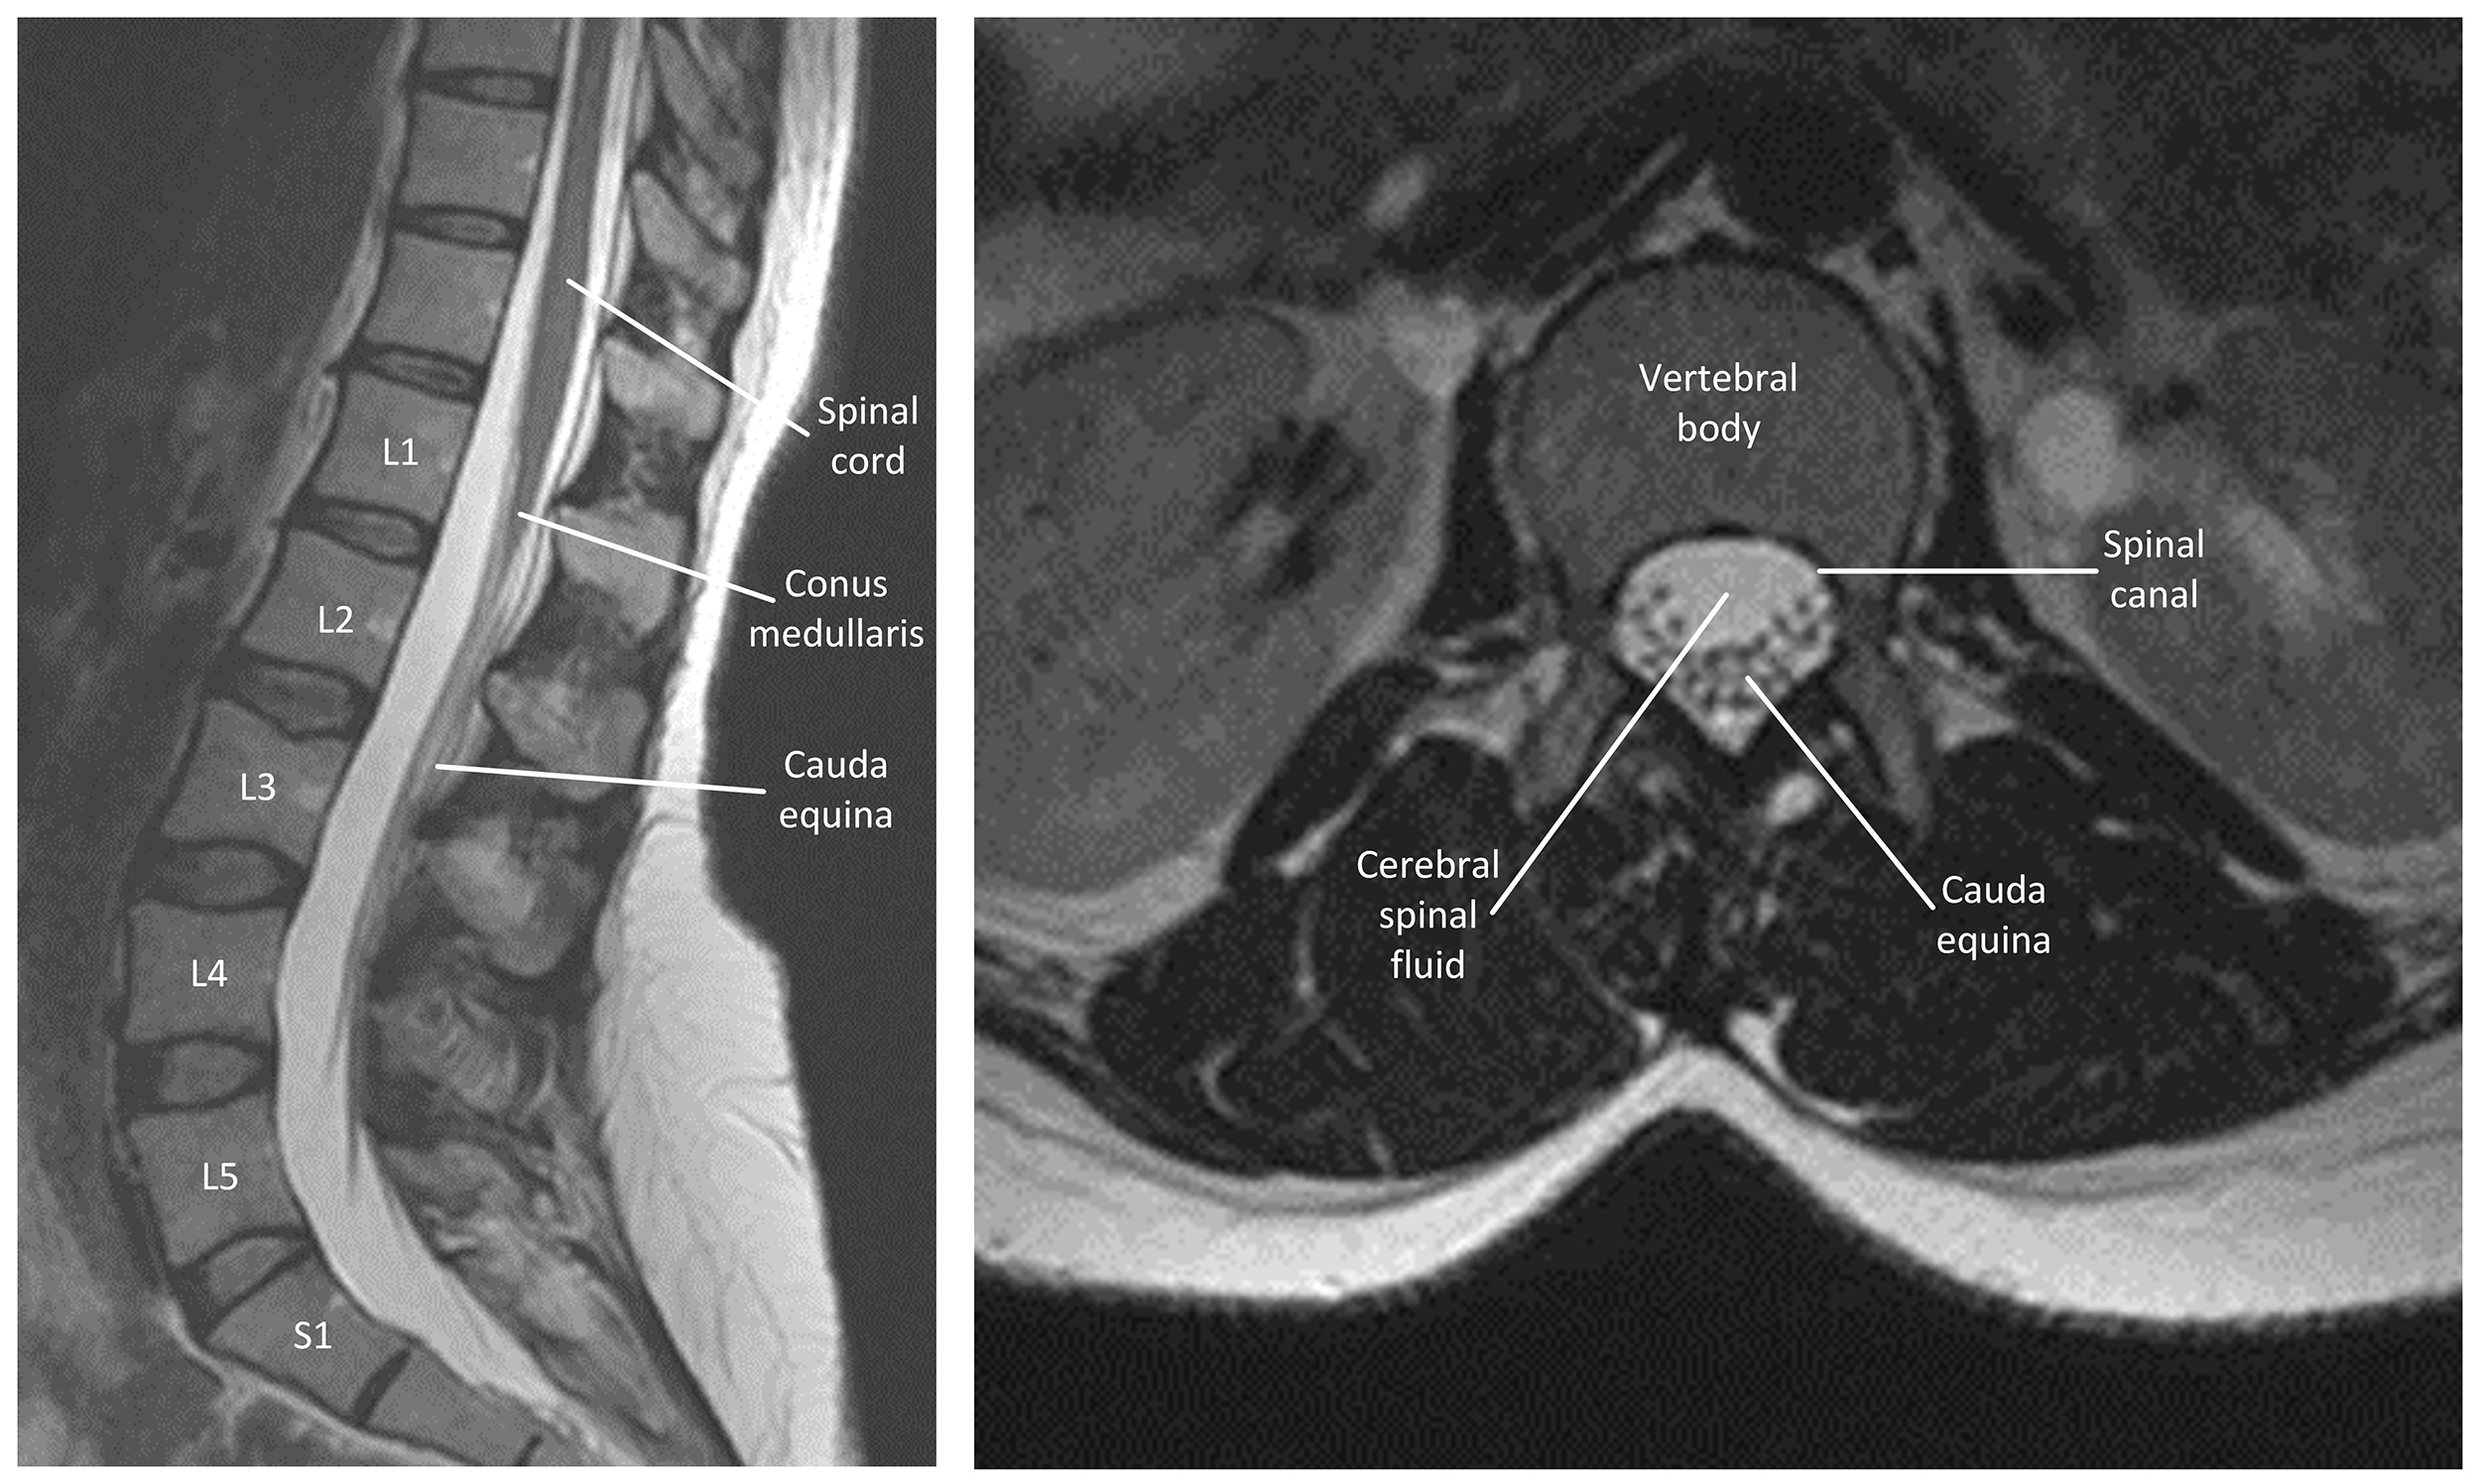

The spinal cord terminates in the conus medullaris at the vertebral levels L1–L2 [14]. Spinal nerve roots then descend distally from this structure to form the cauda equina between L2–S5 (Fig. 1). The cauda equina is protected by the three meningeal layers, the dura mater, arachnoid mater, and pia mater, filled with cerebrospinal fluid within the lumbar cistern of the spinal canal [14].

Fig. 1.

T2 weighted magnetic resonance images of a normal lumbar spine. The left sagittal image shows the spinal cord, conus medullaris, cauda equina and normal lumbar spine. The right axial image shows the L3 vertebral body and cauda equina in the vertebral canal. The image does not contain any identifiable patient data, therefore informed consent is not required.

The cauda equina contains dorsal root afferent fibres to provide sensory transmission for touch, proprioception, temperature, vibration and temperature, and ventral root efferent fibres for motor innervation to sphincters, perineum and legs as well as preganglionic parasympathetic fibres S2–S4 that innervate the bladder and sexual organs [15]. Each nerve root exists distally through the neural foramen directly below the same numbered pedicle.